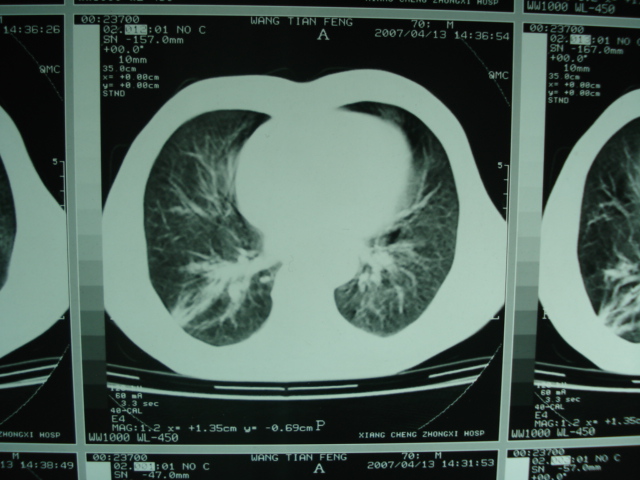

以下是引用狙击手在2007-4-18 20:17:00的发言:[br]原:2007/1/22号ct片:右肺上叶可见片状、云雾状高密度影,右肺上叶后段可见三角形高密度影,尖端指向肺门,右肺上叶后段支气管壁不规则增厚,管腔不规则增厚,纵隔未见肿大淋巴结.[br] 今ct:右肺上叶片状影增大,右肺上叶后段不张及右肺上叶后段支气管壁不规则增厚未见变化,右肺下叶背段支气管壁不规则增厚.[br] 如果考虑肺结核,但从临床证据看竟然没有一项支持肺结核,不知患者是否已经过正规抗结核治疗。没有的话,3个月了前后片看起来变化不大,似乎有不太符合肿瘤征象,不知患者是否抗炎治疗过,下叶支气管增粗还是要高度警惕,同意楼主意见,将常规病理,生化检查再做一遍。[br]

以下是引用狙击手在2007-4-18 20:17:00的发言:[br]原:2007/1/22号ct片:右肺上叶可见片状、云雾状高密度影,右肺上叶后段可见三角形高密度影,尖端指向肺门,右肺上叶后段支气管壁不规则增厚,管腔不规则增厚,纵隔未见肿大淋巴结.[br] 今ct:右肺上叶片状影增大,右肺上叶后段不张及右肺上叶后段支气管壁不规则增厚未见变化,右肺下叶背段支气管壁不规则增厚.[br] 如果考虑肺结核,但从临床证据看竟然没有一项支持肺结核,不知患者是否已经过正规抗结核治疗。没有的话,3个月了前后片看起来变化不大,似乎有不太符合肿瘤征象,不知患者是否抗炎治疗过,下叶支气管增粗还是要高度警惕,同意楼主意见,将常规病理,生化检查在做一遍。[br]